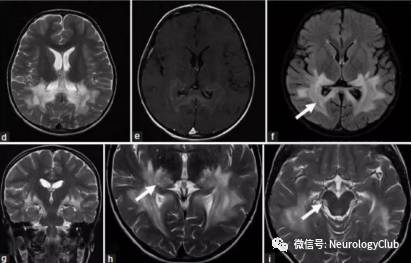

影像学表现可分为四型:顶枕型,全脑分水岭型,额上回型和中央变异型。影像学分型和水肿严重程度都不与临床表现分型和严重程度相关。额叶和颞叶受累者约占75%。累及基底节和脑干者有1/3,累及小脑者约占半数。这些部位的水肿一般是伴随着顶枕部位的受累。病变不累及顶枕区域者少见。仅累及单侧大脑和孤立性脑干与小脑水肿者需要排除其它疾病。

(图3:均为黑水像;A-C:顶枕型PRES;D-F:全脑分水岭型PRES;G-I:额上回型PRES)

(图4:均为黑水像;中央变异型PRES